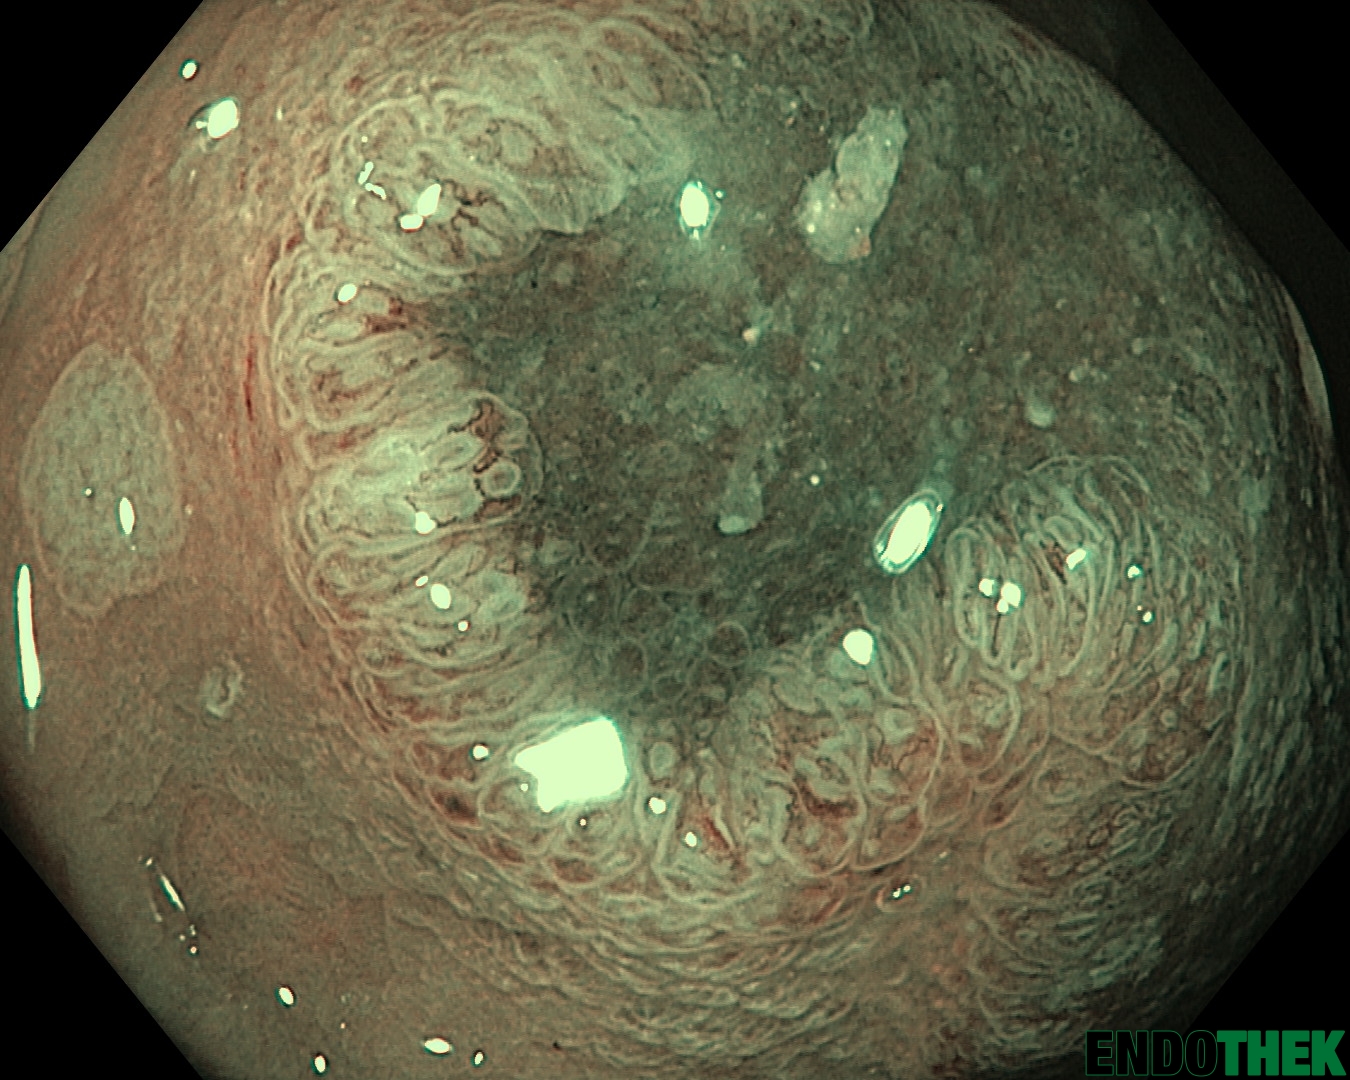

The Endothek is a source for endoscopic pictures and videos. Such instrument did’t exist in Austria for a long time and I try to change this. The whole platform is community driven and everyone can participate and benefit from it.